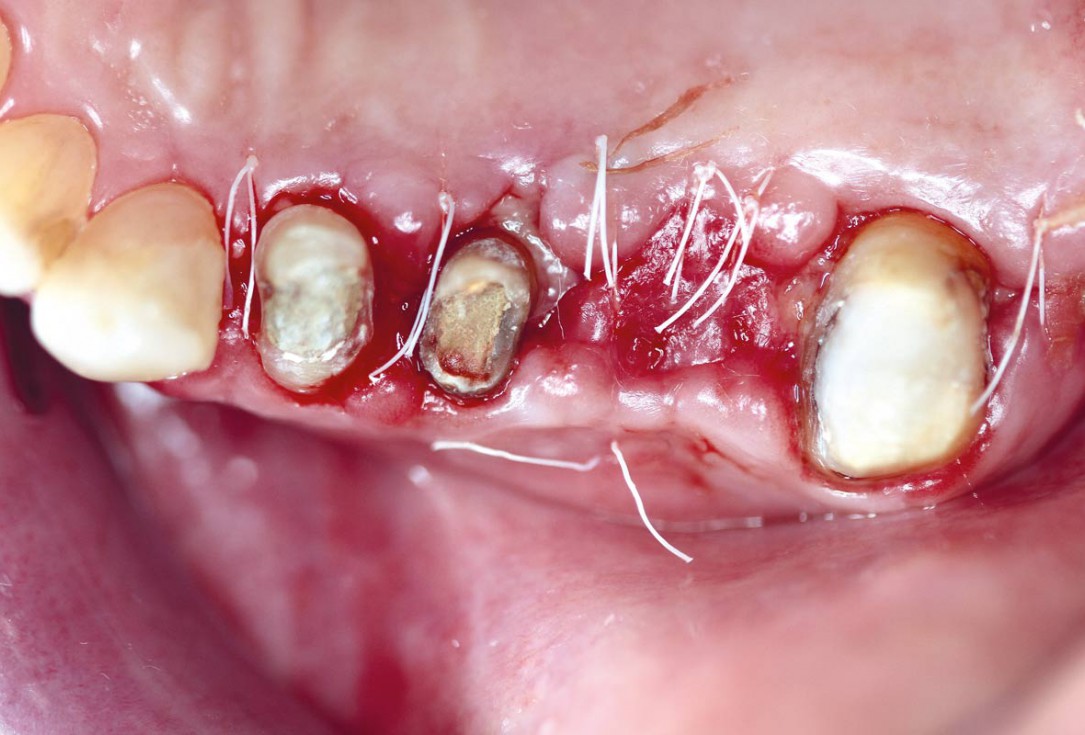

botiss cerabone® & collprotect® membrane for GBR - Clinical case by Dr. V. Kalenchuk

Clinical situation with narrow alveolar ridge in the lower jaw